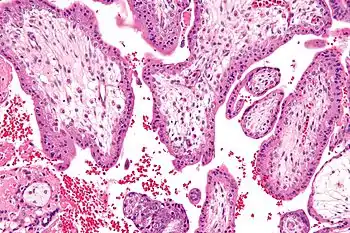

![]() | |

| Child with Smith-Lemli-Opitz syndrome | |